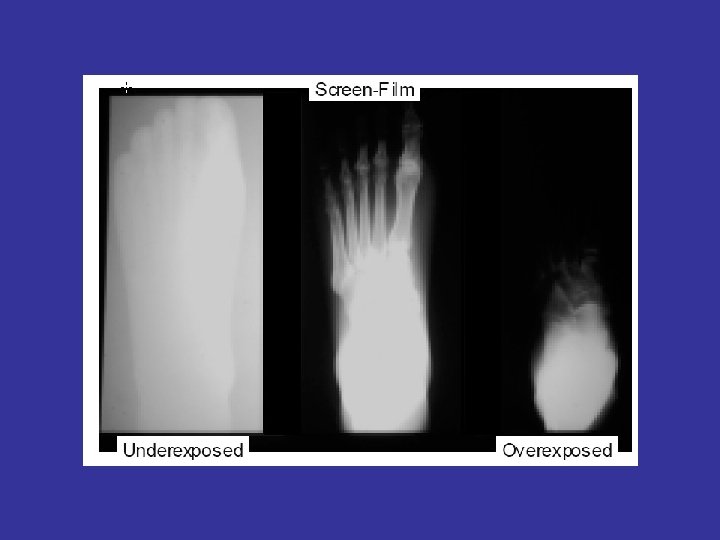

• By adjusting image brightness and/or contrast, a wide range of thicknesses may be examined in one exposure, unlike conventional film based radiography, which may require a different exposure or multiple film speeds in one exposure to cover wide thickness range in a component. Computed radiography often requires fewer reshots due to under- or over-exposure. • Images can be enhanced digitally to aid in interpretation.